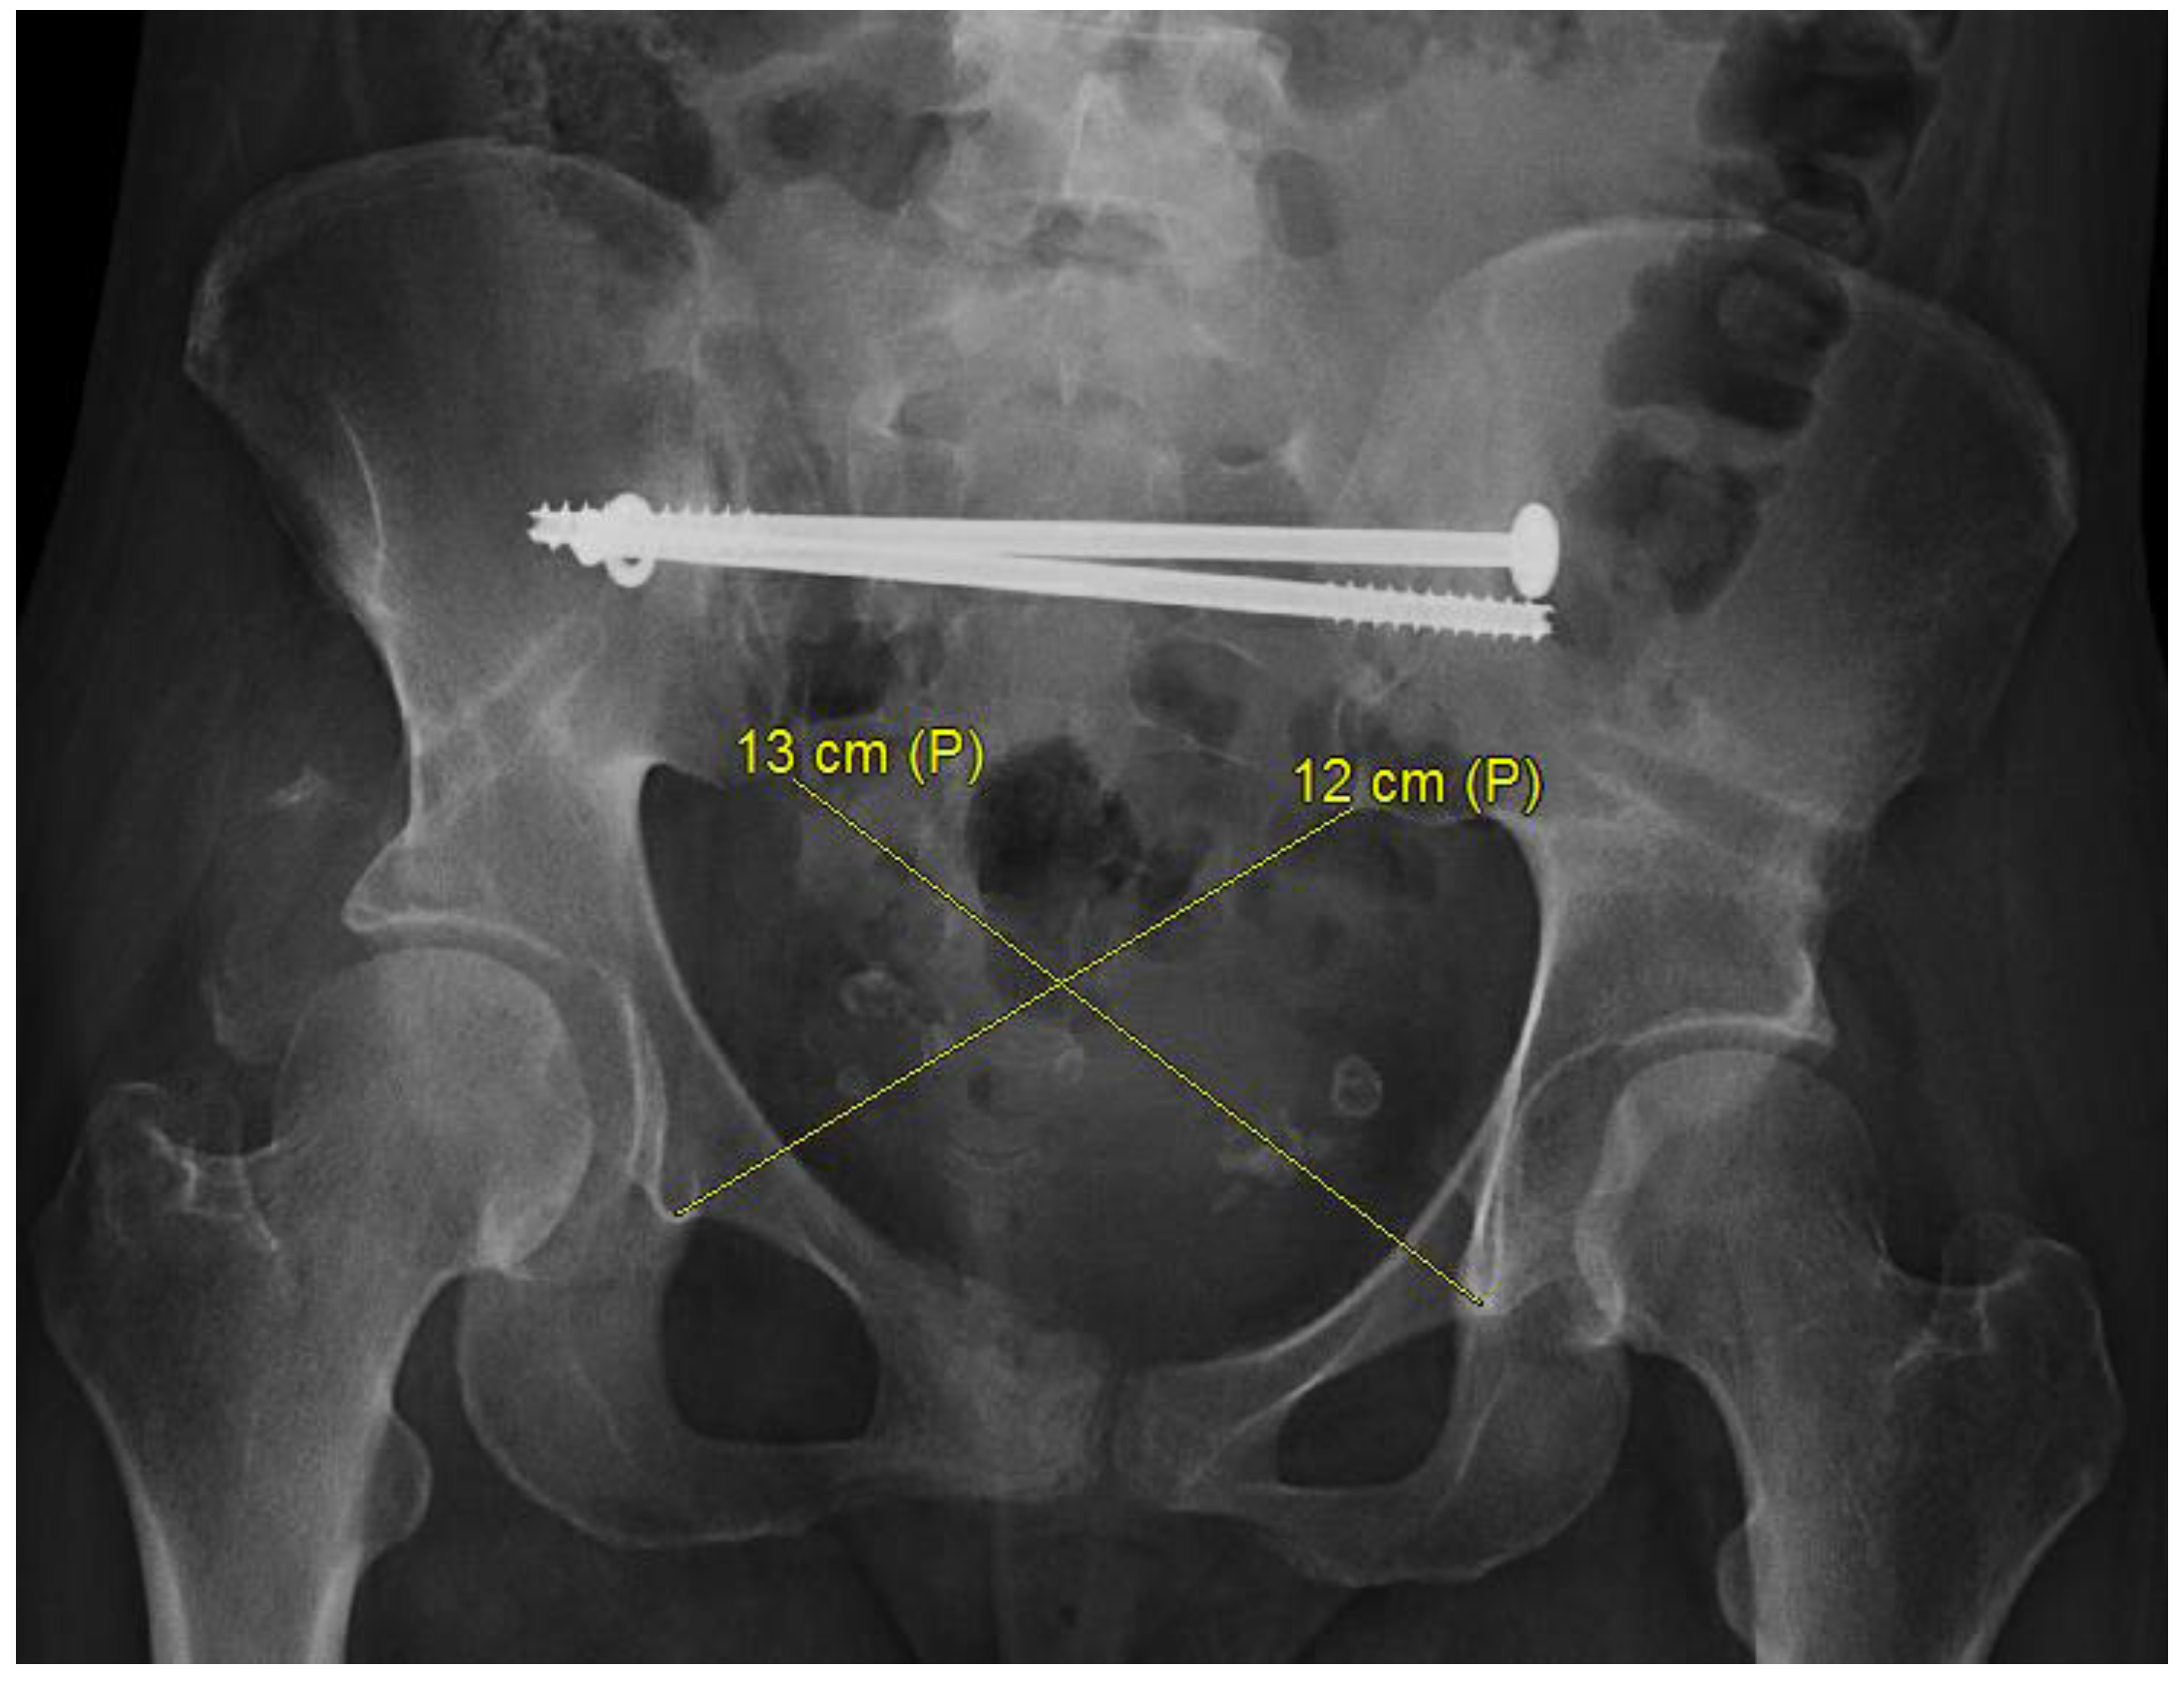

- Herteleer, M.; Thüroff, J.; Rommens, P.M. Single stage reconstruction of a neglected open book pelvic injury with bladder herniation into the upper thigh: A case-report. Arch. Orthop. Trauma Surg. 2021, 141, 855–859, Correction in Arch. Orthop. Trauma Surg. 2021, 141, 1629. [Google Scholar] [CrossRef]